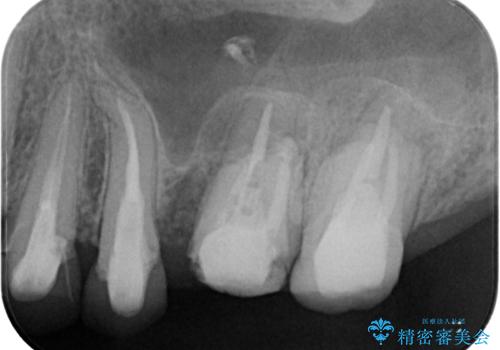

- 奥歯のクラウンが土台ごと外れてしまったとのことで来院された患者様です。

保存可能ではありましたが、予後不良と患者様ご自身が判断されており、相談の結果抜歯即時埋入インプラントによる補綴治療を行うこととしました。

垂直方向への炎症が大きく、抜歯即時埋入はできたものの、即時荷重(インプラント埋入時の仮歯の装着)を可能とする安定値は得られませんでした。